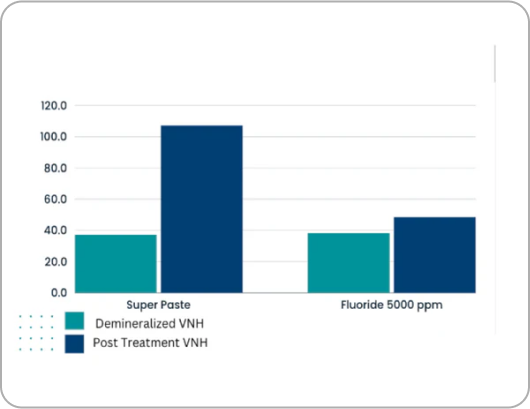

6x More Effective than 5000 ppm Fluoride Toothpaste in Xerostomia Environments

In a recent study, Dr. Jen's Super Paste demonstrated 6x higher levels of remineralization compared to high prescription fluoride toothpaste in dry mouth conditions (xerostomia).